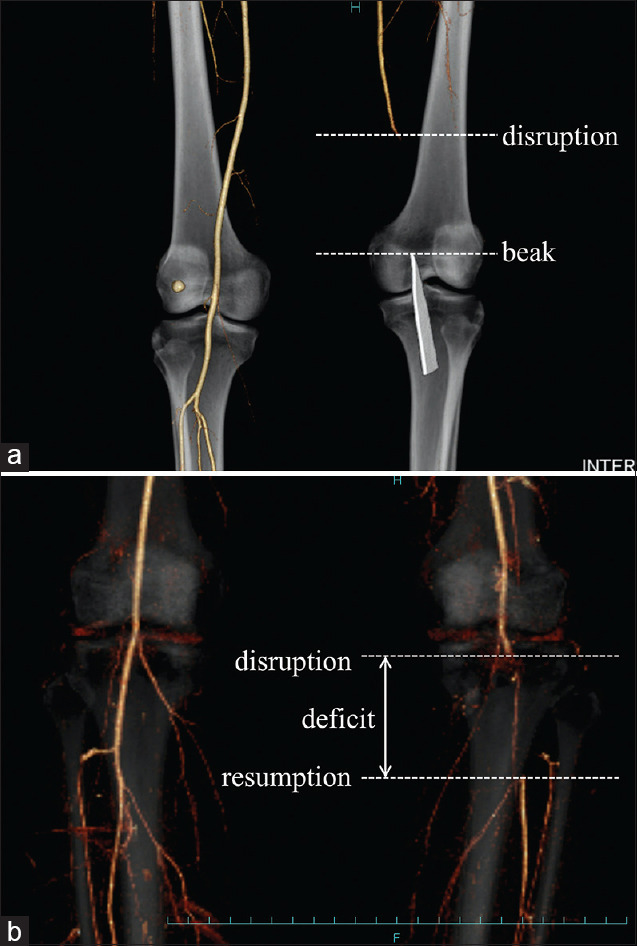

Results: Group A included seven patients (dislocations, n = 3; fractures, n = 2; and glass penetration injuries, n = 2), with a mean follow-up period of 39 months. Group B included five patients (dislocations, n = 3 and fractures, n = 2), with a mean follow-up period of 36 months. Two patients in Group A and four patients in Group B exhibited contrast-medium resumption (average deficit: 57 mm and 60 mm, respectively). The time from injury to reperfusion was significantly shorter in Group A than in Group B (300 min vs. 749 min, P < 0.05). Group A underwent four temporary vascular shunting procedures, four external fixations, six fasciotomies, and five bypass grafting procedures. In Group B, temporary vascular shunt (TVS) was not used in any patient; however, three, two, and three patients underwent external fixation, fasciotomy, and bypass grafting, respectively. One patient in each group required above-the-knee amputation. The mean Lysholm score was 80.4 points in Group A and 72.0 points in Group B.